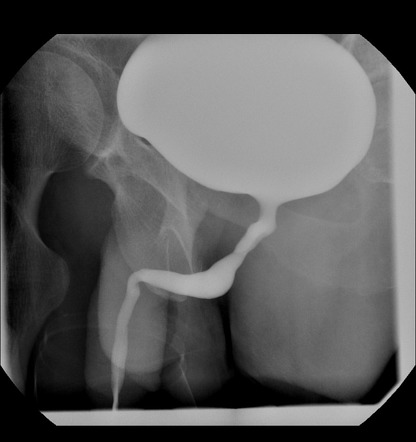

Chụp niệu đạo bàng quang thì bài xuất không được khuyến cáo trong các xét nghiệm thường quy chẩn đoán LUTS. Tuy nhiên, phương tiện này lại được chỉ định trong một số trường hợp nghi ngờ như trào ngược bàng quang - niệu quản, túi thừa bàng quang hoặc các bệnh lý về niệu đạo (hẹp niệu đạo, van niệu đạo).

Chụp bàng quang - niệu đạo thì bài xuất (VCUG)